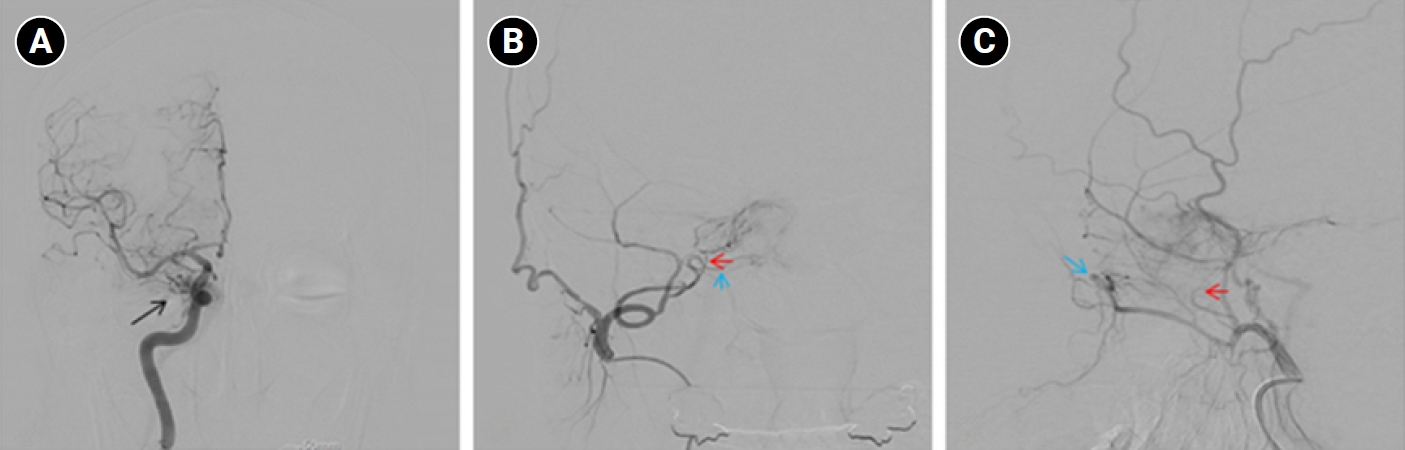

Baseline hematology and chemistry—including complete blood count, electrolytes, renal/hepatic indices—and coagulation tests (prothrombin time/international normalized ratio, activated partial thromboplastin time) were within reference limits. Erythrocyte sedimentation rate and C-reactive protein were normal. A focused screen for secondary trigeminal neuropathy (thyroid-stimulating hormone, vitamin B12, HbA1c) was negative. There were no clinical signs of infection. Brain magnetic resonance imaging (MRI) demonstrated high flow related signal in the right cavernous sinus and asymmetric dilation of the superior ophthalmic veins (right>left), raising suspicion for a CCF (Figure 1). Definitive diagnosis was established on digital subtraction angiography (DSA), which identified a right CCF. DSA demonstrated an indirect CCF supplied by the right meningohypophyseal trunk of the ICA and by right ECA branches, including the internal maxillary artery and the cavernous branch of the middle meningeal artery, consistent with Barrow type D (Figure 2).6 Barrow type D denotes an indirect, low-flow fistula with dual ICA/ECA dural supply; unlike direct type, indirect types present more insidiously, and symptom patterns are largely determined by venous drainage, with posterior drainage often manifesting as CN VI palsy and headache (Table 1).1,3,6,7 The fistula was treated with transvenous Onyx embolization. On post-procedure day 1, non-contrast time-of-flight magnetic resonance angiography (TOF-MRA) demonstrated a marked reduction of flow related hyperintensity within the right cavernous sinus, and the right superior ophthalmic vein caliber decreased from 6.63 to 4.61 mm (Figure 3A, B). Follow-up DSA (at 3 weeks) likewise showed substantial attenuation of fistulous opacification (Figure 3C), supporting a significant interval decrease in arteriovenous shunting. At 1–2 weeks, the patient reported an ~80%–90% reduction in dental/lower-facial pain and bifrontal headache from NRS 7–8 to 1–2. By 1 month, red-glass testing demonstrated resolution of primary-position diplopia. Formal prism measurements were unavailable; bedside ocular-motor grading was recorded using a standard duction underaction scale (–4 to 0). Right abduction improved from –1 to 0, and primary-position diplopia was absent at distance and near, consistent with recovery from abducens palsy.

Figure 2.Digital subtraction angiography findings in the patient. (A) Right internal carotid artery (ICA) angiogram shows an indirect carotid-cavernous fistula supplied by the meningohypophyseal trunk of the cavernous ICA (black arrow). (B, C) Right external carotid artery angiogram demonstrates additional arterial supply from external carotid branches, including the internal maxillary artery (blue arrows) and the cavernous branch of the middle meningeal artery (red arrows).